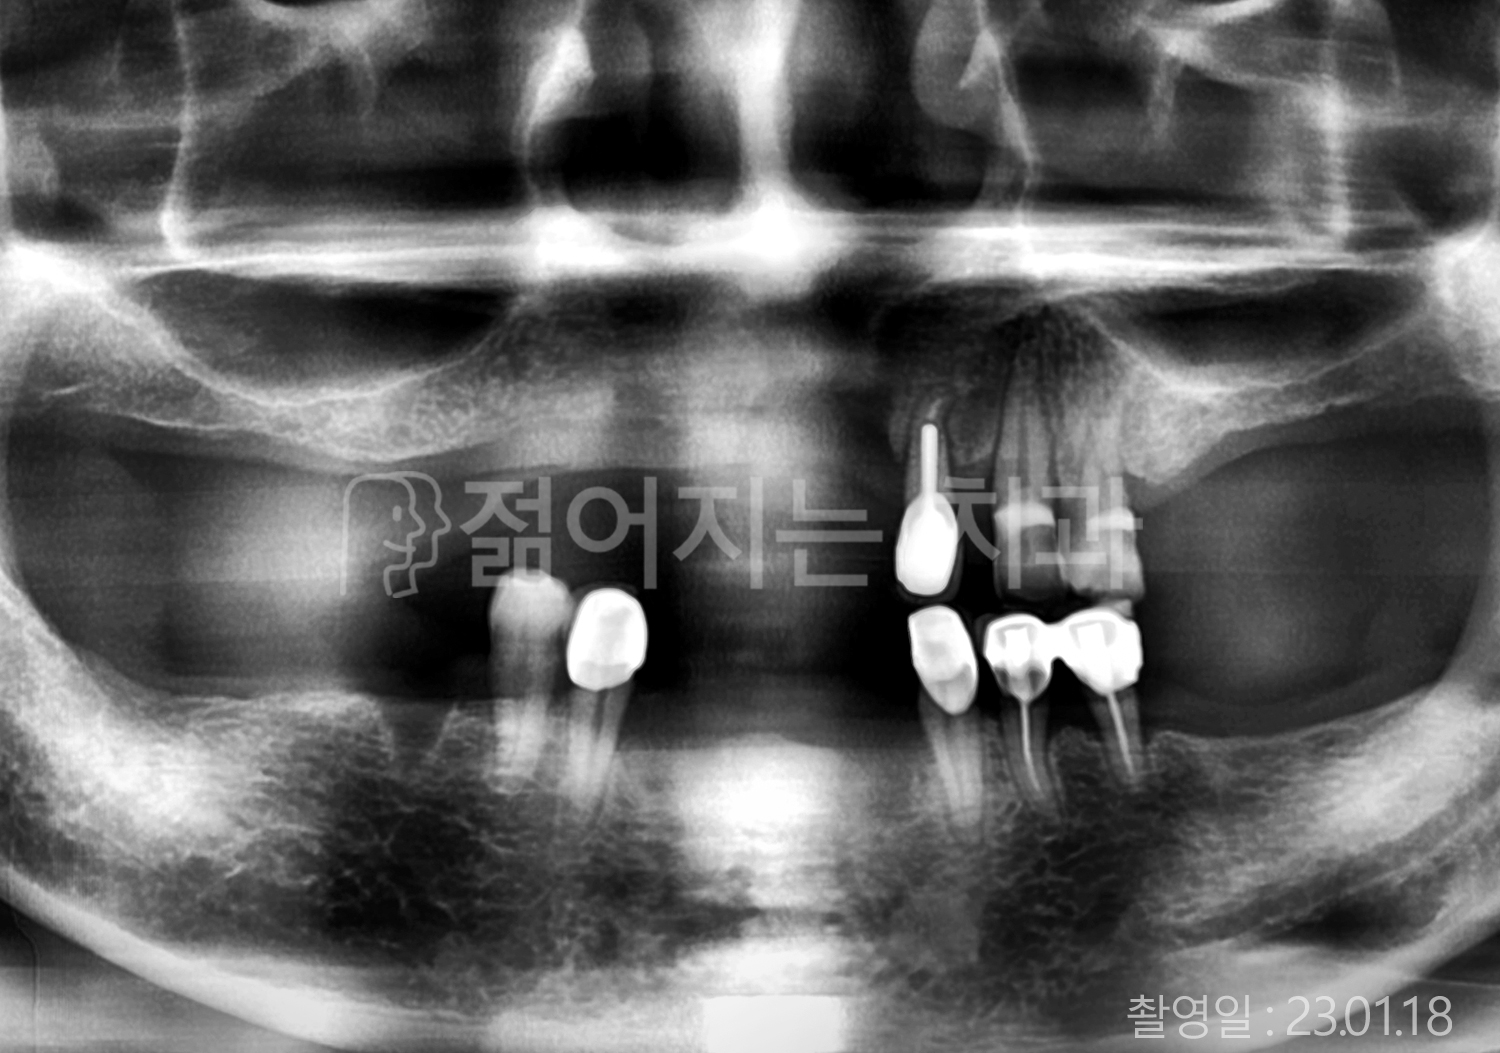

• 70대 고혈압, 고지혈증 전체치아 10개 이상 임플란트

• 60대 당뇨, 간염 전체치아 10개 이상 임플란트

• 80대 골다골증 전체치아 6개 이상 임플란트

• 70대 고혈압, 당뇨 전체치아 10개 이상 임플란트

• 60대 간 질환 전체치아 10개 이상 임플란트

• 60대 전체치아 10개 이상 임플란트

• 70대 전체치아 10개 이상 임플란트

• 50대 전체치아 10개 이상 임플란트

• 60대 고혈압, 고지혈증 전체치아 10개 이상 임플란트

• 40대 고지혈증, 뇌혈관 질환 전체치아 10개 이상 임플란트